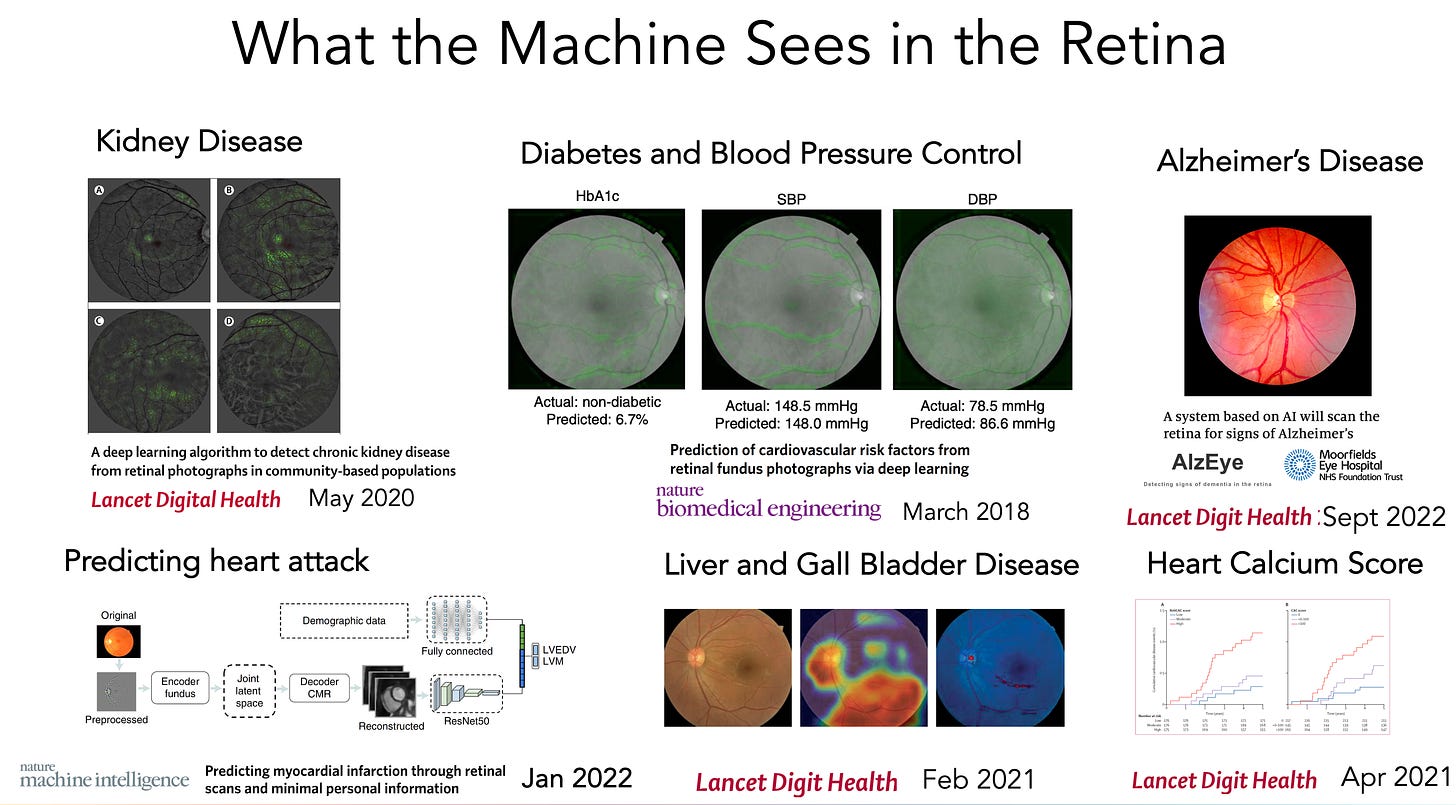

First, a review on deep learning from the retina. We should have known a few years back that something was rich (dare I say eye-opening) about the retina that humans, including retinal experts, couldn’t see. While there are far simpler ways to determine gender, it’s a 50-50 toss up for ophthalmologists, which means there are no visible cues to human eyes. But now two models have shown 97% accuracy of gender determination from neural network training. That was just the beginning.

Of course, AI models have been shown to be quite useful for detecting eye diseases, such as diabetic retinopathy. But this is about the indirects, the not so obvious. That work has now extended to detection of kidney disease, control of blood glucose and blood pressure, hepatobiliary disease, a previous study on predicting heart attack, close correlation of the retinal vessels with the heart (coronary) artery calcium score, and, prior to the new report above, the ongoing prospective assessment and tracking of Alzheimer’s disease (“AlzEye,” Moorfields Eye Institute, UK, led by Professor Pearse Keane).

Nearly all of this work has been published in the last couple of years, and there’s no telling what else can be seen by machines that would be invisible to human eyes. Therein lies the future potential for taking a photo of your retina via your smartphone (ideally without having to dilate your pupils) to get an accurate readout of many of your body systems/ organ functions.